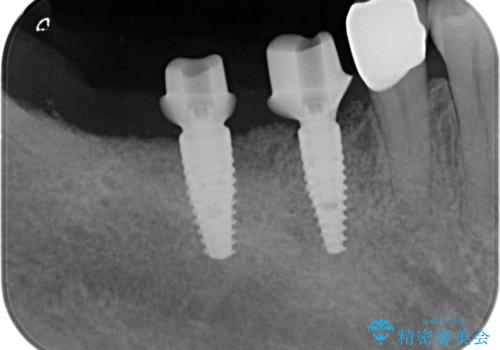

歯周病や虫歯・強度の問題がありながらも無理やり残していた長期的な予後の見込めない歯を抜去し、インプラントを用いてしっかりと噛めるような口腔内環境の確立を目指します。

- 176万円(インプラント×4・チタンカスタムアバットメント×4・ジルコニアクラウン×4・仮歯×4)費用は治療当時の料金となります

見た目が白くなり喜んでいただけただけでなく、しっかりとした噛めるようになり食事を不安なく楽しんでいただけるようになりました。